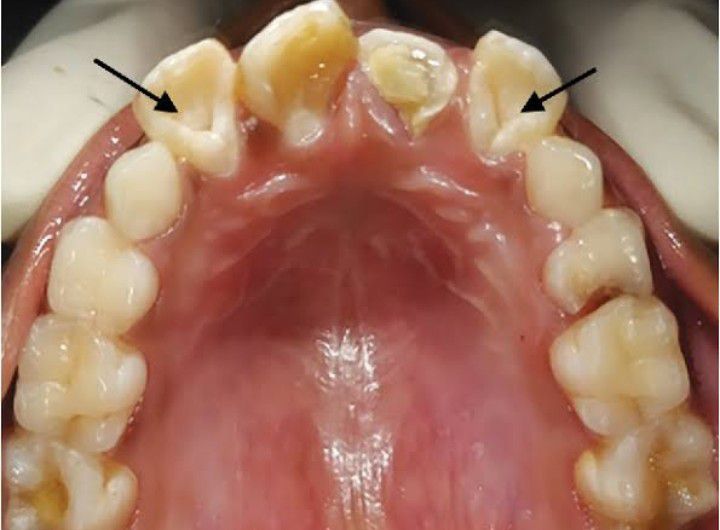

Dens invaginatus

Dens in dente is a rare dental anomaly. It occurs when the enamel folds into the dentin during tooth development.